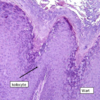

lichen planus

pruritic

purple

polygonal

papules

Wickam striae

symmetric distrubution

30-60 yo

hepatitis C, medication, contact allergen